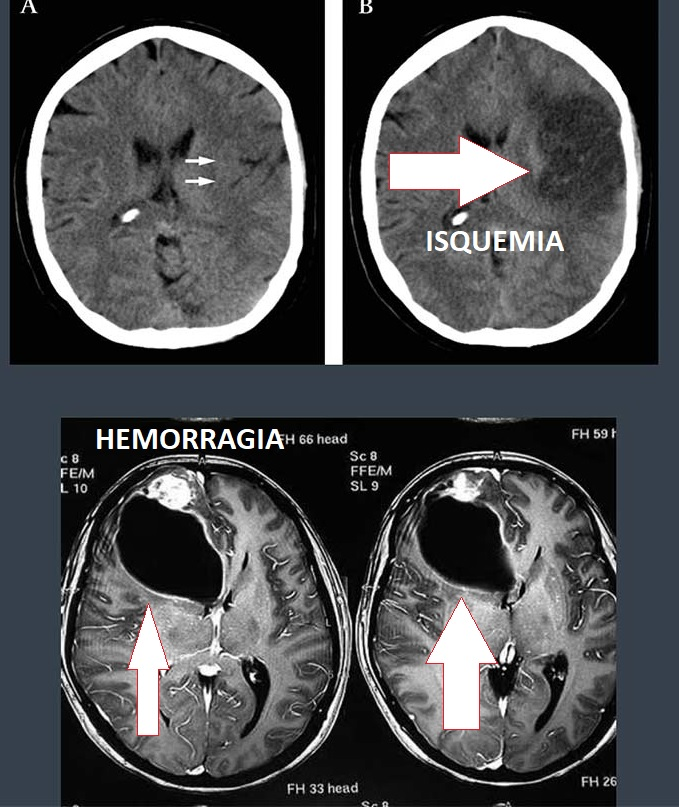

Para el diagnóstico del accidente cerebrovascular isquémico y hemorrágico, se utilizan estudios de imagen de alta calidad, como lo son la tomografía y la resonancia magnética transcraneal.

Manifestaciones clínicas de las hemorragias intracerebrales según el Atlas de neuroanatomía de Frank Netter.